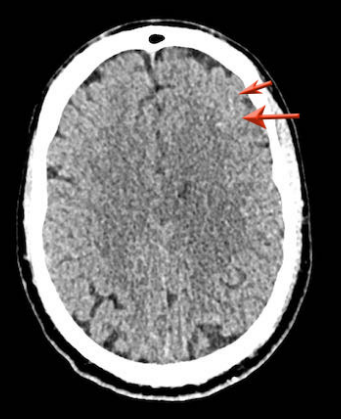

下图一例硬膜下血肿,很难发现(箭头)。

注意,在较高的水平上有双侧硬膜下血肿。